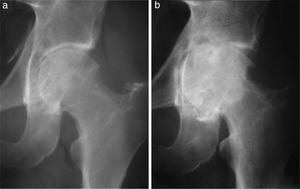

Fourteen patients (40%) developed osteoarthritis secondary to TGCT. The mean age for the development of osteoarthritis in our patients was 57.4 years (median: 58 years; range: 34.83), with this being the most frequent in patients ≥50 years (N=8; p=.031). However, there was a considerable number of patients under 50 years of age who developed osteoarthritis (N=6). Mean time from TGCT diagnosis to the development of osteoarthritis observed in our patients was relatively short: 39 months (median: 37 months; range: 7–122). Seven patients affected with osteoarthritis (50%) required surgical treatment by arthroplasty or arthrodesis of the affected joint. Of these 7, 6 (85.71%), presented with a TGCT-D (p=.01). One of them required an arthrodesis of the ankle at 46 years of age as initial treatment for TGCT and another required a total hip replacement at 33 years of age, due to joint destruction from a TGCT-D recurrence (Fig. 1). In our series, we observed that it was more common to develop osteoarthritis of the hip (100%) and ankle (50%), than the knee (26%; p=.03). We also saw that the duration of the symptoms prior to diagnosis and treatment of the TGCT had a negative impact n the development of the osteoarthritis. There is a difference of 16.2 months in the duration of the symptoms between those who developed osteoarthritis and those who did not (p=.05). The development of osteoarthritis is not associated in any statistically significant way with primary bone involvement (p=.28), with the development of local recurrence (p=.43), with type of surgery (open or arthroscopic), performed on the primary tumour (p=.086), or the total number of operations the patents had undergone (p=.061).

(a) Male aged 32 years with a 5 year history of pain and functional limitation in the left hip. Open surgical synovectomy was performed. (b) A year later he presented with recurrence of the lesion and advanced osteoarthritis for which finally, at the age of 33, he required a total hip arthroplasty.